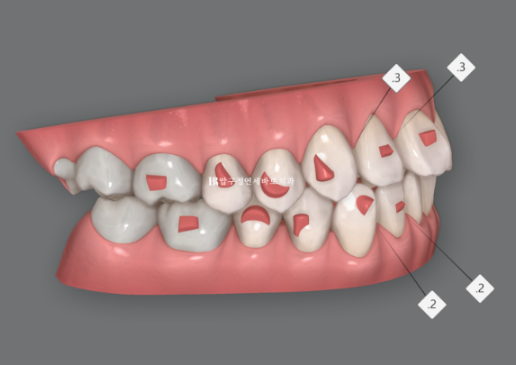

인비절라인 치료계획을 클린체크라고 부릅니다.

이 환자분의 클린체크를 보겠습니다.

앞니 부분교정에서 치아가 배열될 소량의 공간을 얻는 목적, 그리고 성인들 교정 후 필연적으로 생기는 블랙트라이앵글 축소를 위한 목적의 두 가지 목적으로 치간삭제를 앞니 사이사이 부위당 0.2~0.3mm씩 배치하였습니다.

클린체크에서 한가지 더 주목할 점은 좋은 어금니 교합을 유지하기 위해서 큰 어금니의 위치를 이동없음 으로 설정해 놓는 것입니다.

진회색으로 표시된 치아가 치료 전 후 이동이 전혀 없는 치아가 됩니다.

이 이동없음 설정이 필요한 경우는 꽤 많습니다.

이 환자분과 같이 7단계 안에 좋은 결과를 얻기 위해 불필요한 치아이동량은 최소화 하기 위해서이기도 하고 임플란트가 있는 경우라면 임플란트 치아를 이동없음으로 해놓기도 합니다.